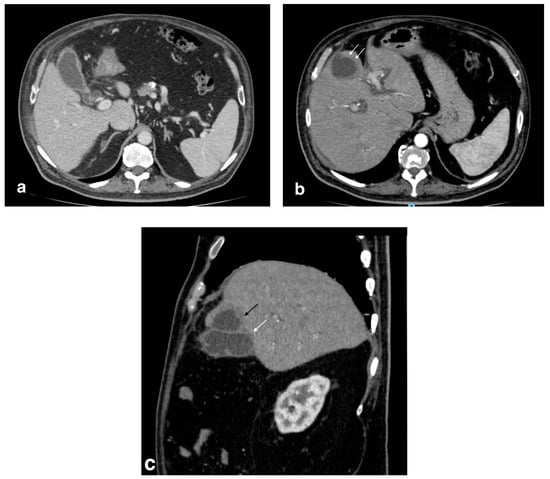

Figure 3.

Emphysematous cholecystitis: (a) Ultrasonography: diffuse hyperechogenicity due to extended reverberation artifact with poor gallbladder lumen resolution. (b) CT findings: gallbladder wall thickening with intramural air (white arrows). CT was able to detect and characterize the disease.